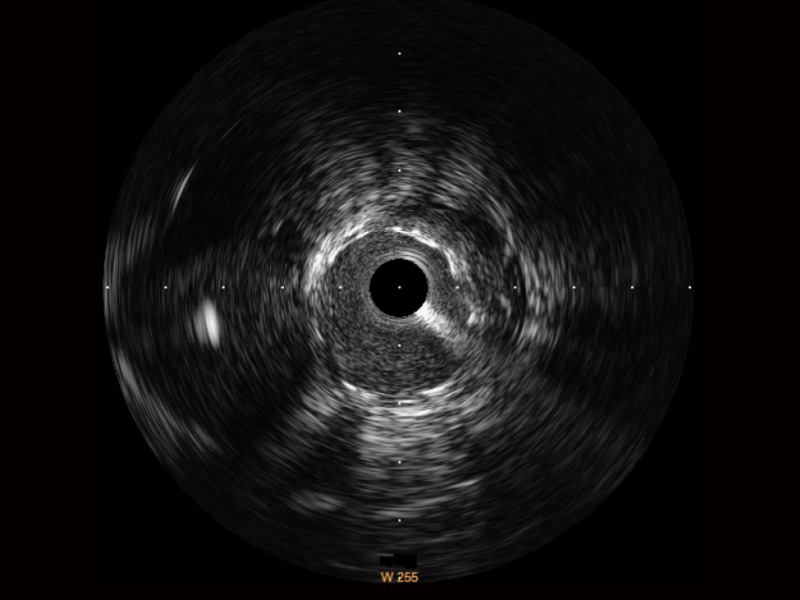

米兰官方网站宽频IVUS图像

传统IVUS图像

对比传统IVUS导管成像,米兰官方网站宽频IVUS图像的近场支架梁显影更细腻,远场中膜外血管仍清晰可辨,兼顾远中近,兼顾分辨力与穿透深度